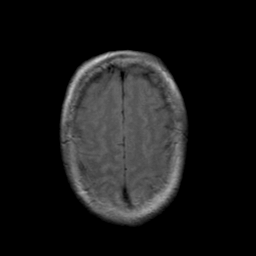

Stroke: proton density-weighted MR #2 -- Slice #20

[Home][Help][Clinical] Slice 20